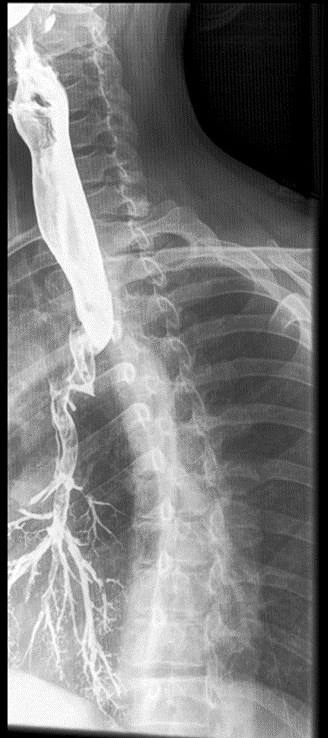

Tracheoesophageal Fistula

Congenital form – results from the failure of the esophageal lumen to develop completely separate from the trachea.

Acquired type – caused by cancer, infection, trauma, instrumentation perforation.

Radiological Appearance: